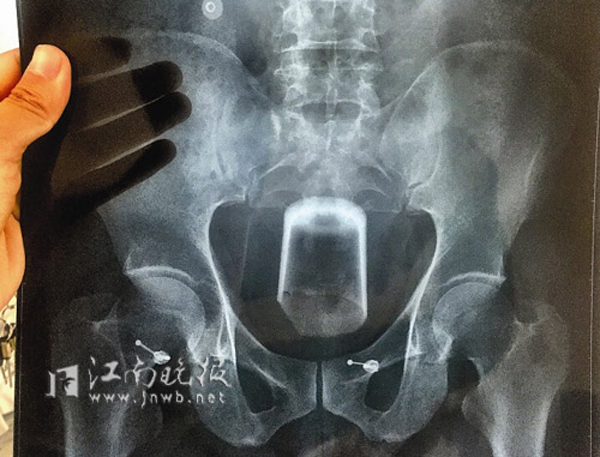

เว็บไซต์เดลี่เมลของอังกฤษ รายงานเมื่อวันที่ 1 มิถุนายน 2558 ว่า ชายจีนสุดซวย อุตริยัดแก้วเบียร์ขนาดกว้าง 3 นิ้ว เข้าไปในรูทวารหนัก หวังรักษาอาการท้องผูก แต่แล้วแก้วเบียร์กลับติดคาอยู่ในนั้นเอาออกไม่ได้ สร้างความเจ็บปวดทรมานอย่างมาก ในที่สุดจึงต้องโร่ไปหาหมอเพื่อให้ช่วยเอาแก้วเจ้ากรรมดังกล่าวออกมาจากทวารหนักให้

เหตุการณ์นี้เกิดขึ้นในเมืองอู๋ซี ทางตะวันออกของประเทศจีน ชายจีนรายนี้ซึ่งไม่ได้รับการเปิดเผยชื่อถูกนำตัวส่งโรงพยาบาลกลางอู๋ซี หลังจากยัดแก้วเบียร์เข้าไปในรูทวารแต่ดันเอาออกไม่ได้ เขาถูกส่งเข้าห้องฉุกเฉินทันทีด้วยอาการเจ็บปวดจนใบหน้าขาวซีด และที่นั่นศัลยแพทย์ 3 คนได้ช่วยกันดึงแก้วออกมา แต่มันก็ไม่ได้เป็นไปอย่างง่าย ๆ พวกเขาต้องใช้เวลานานเป็นชั่วโมงกว่าจะเอาแก้วออกมาได้ และแก้วเบียร์เจ้ากรรมนั้นก็แตกทันทีที่ออกมาจากทวารหนักของผู้ป่วย เนื่องจากแรงดึงของศัลยแพทย์ทั้ง 3 ราย

จากการสอบถามผู้ป่วยชายรายนี้ เขาเล่าให้แพทย์ฟังว่า เหตุผลที่เขายัดแก้วเข้าไปในทวารหนักของตัวเองนั้น ก็เพื่อรักษาอาการท้องผูก แต่แล้วเรื่องไม่คาดคิดก็เกิดขึ้นเมื่อมันลื่นหลุดเข้าไปติดอยู่ในทวารหนักอย่างนั้น พร้อมกันนี้เขายังเปิดเผยว่าก่อนหน้าที่จะมาพบแพทย์ที่โรงพยาบาลกลางอู๋ซี เขาได้ไปพบแพทย์ที่โรงพยาบาลอีกแห่งมาก่อน แต่แพทย์ที่นั่นไม่สามารถนำแก้วออกมาจากทวารเขาได้ ซ้ำร้ายแพทย์ยังทำขอบแก้วแตกระหว่างการพยายามนำแก้วออกมาด้วย